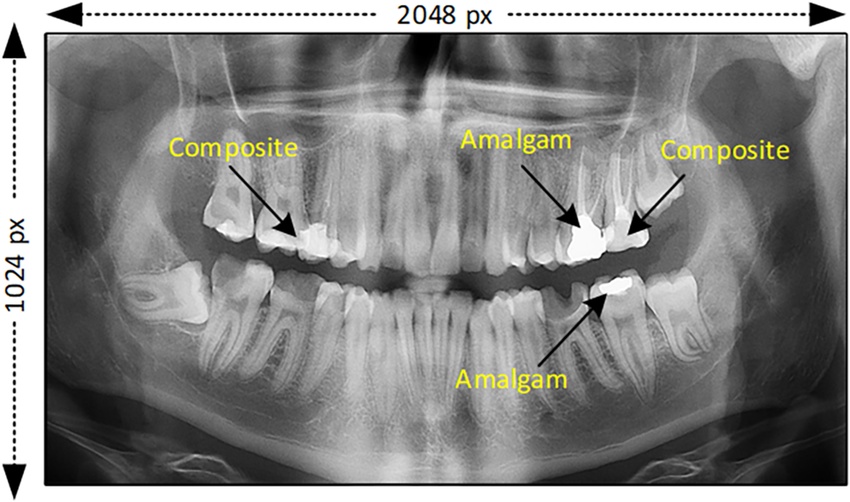

Digital Panoramic X-Ray at Cebu Dental Care Center

Modern dentistry begins with accurate diagnosis—and Digital Panoramic X-Ray technology makes that possible. At Cebu Dental Care Center, we use advanced digital imaging to provide safe, fast, and detailed views of your entire mouth, helping our dentists create precise and effective treatment plans.

What Is a Digital Panoramic X-Ray?

A Digital Panoramic X-Ray is a wide-view dental scan that captures:

This single image gives your dentist a complete overview of your oral health—without the need for multiple X-rays.

Why Digital Panoramic X-Ray Is Important

Accurate Diagnosis

Detects hidden dental problems such as impacted teeth, cysts, tumors, jawbone issues, and infections that may not be visible during a regular exam.